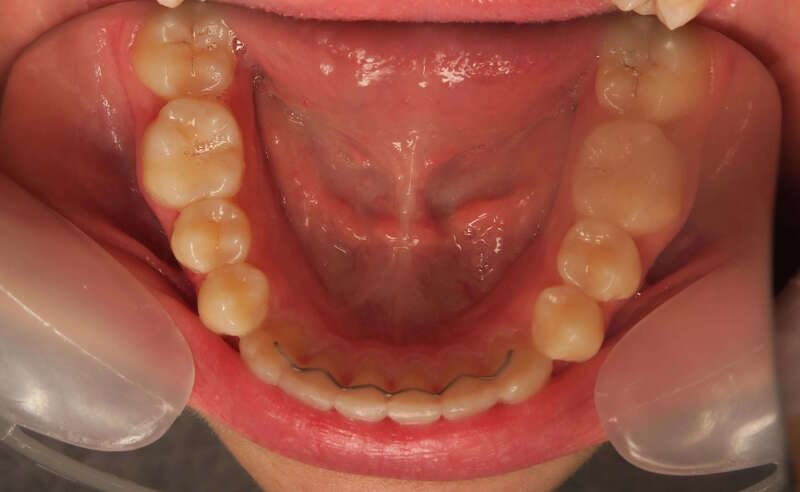

Cas n°1 traité par aligneurs - adolescent

Ce cas d’une adolescente illustre la correction d'une Classe II avec supraclusion par aligneurs. La stratégie thérapeutique a reposé sur une distalisation séquentielle de l'arcade supérieure. Ce mouvement précis a permis de reculer les dents maxillaires étape par étape pour annuler le surplomb (overjet) sans extractions.

Résultats clés :

• Correction fonctionnelle : Retour à un engrènement de Classe I stable et correction du recouvrement vertical.

• Esthétique restaurée : Harmonisation globale du sourire et du profil.

• Approche moderne : Un traitement discret, confortable et hautement prévisible.

Le résultat final montre une occlusion saine et un sourire parfaitement aligné, garantissant une santé dentaire et articulaire optimale pour l'avenir.